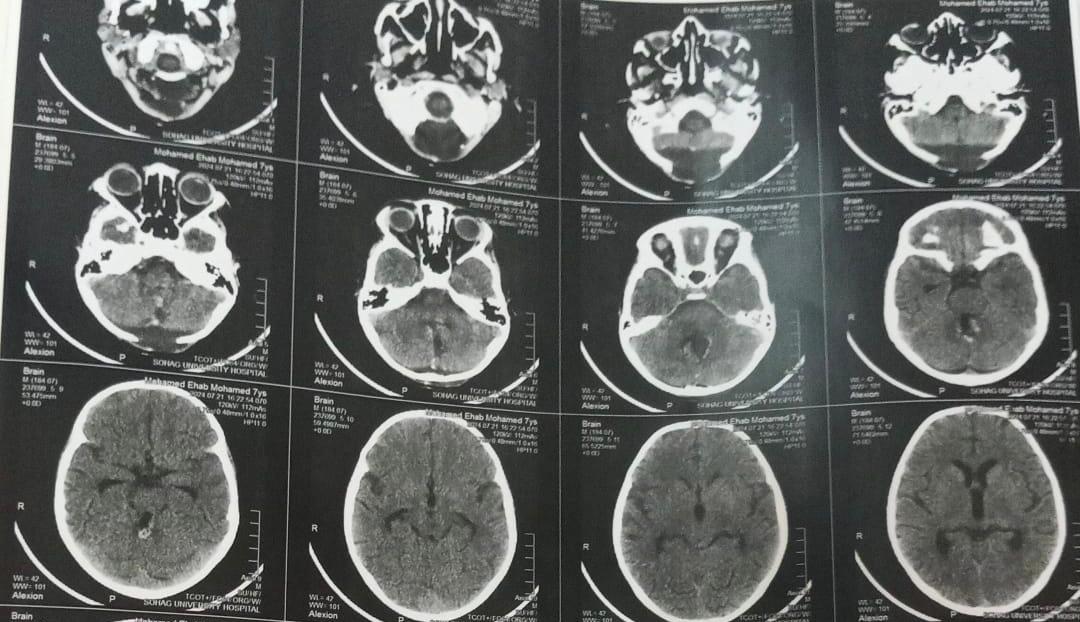

وأضاف الدكتور أحمد كمال مدير مستشفى الجراحات المتخصصة جامعة سوهاج، أنه بعد عمل أشعة الرنين المغناطيسي تبين وجود ورم خبيث بالفص الخلفي من المخ ضاغط على المخيخ وجزع المخ، لافتًا إلى أن هذه الحالات تعتبر من أخطر حالات أورام المخ وقاع الجمجمة لما يحمله الجزء المصاب به الورم من مراكز حساسة.

وأكد الدكتور عابدين خيرالله قاسم رئيس قسم جراحة المخ والأعصاب جامعة سوهاج، أن الفريق الطبي الجراحي نجح في استئصال الورم كليًا مع الحفاظ على المراكز والشرايين المحيطة بالورم للحفاظ على المخيخ وجذع المخ، اعقبها نقل المريض إلى العناية المركزة للأطفال لإفاقة الطفل تدريجيًا، وبعد مرور يوم كامل للإفاقة استعاد الطفل الوعي كاملًا مع حركة الأطراف طبيعيًا.